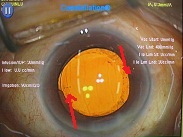

先日ハードレンズを処方した方の写真です。

先日ハードレンズを処方した方の写真です。